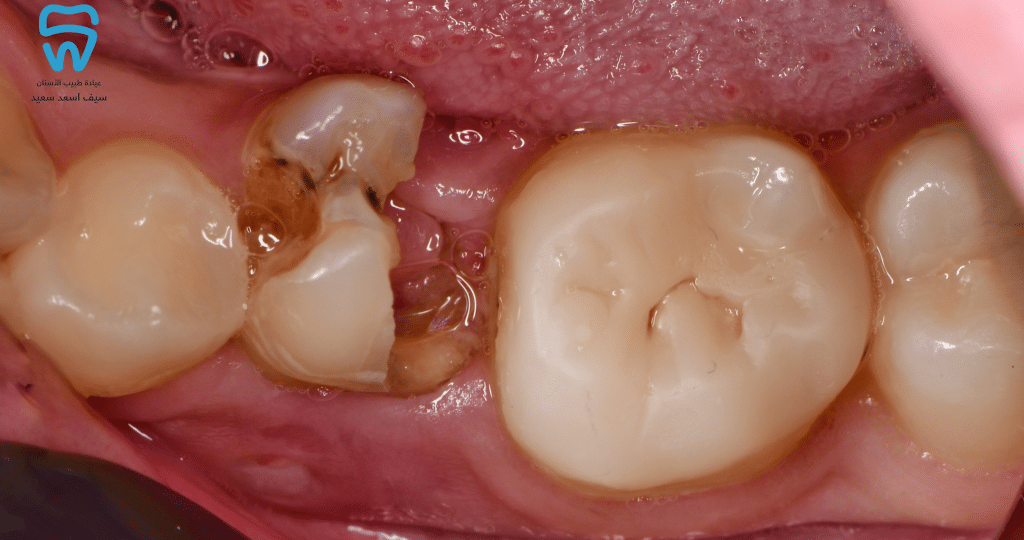

Complete caries excavation with pulp amputation and cessation of haemorrhage.

Placement of MTA over the pulp under isolation

MTA was placed over the pulp, with the absence of symptoms.

Placement of GIC as an interim restoration